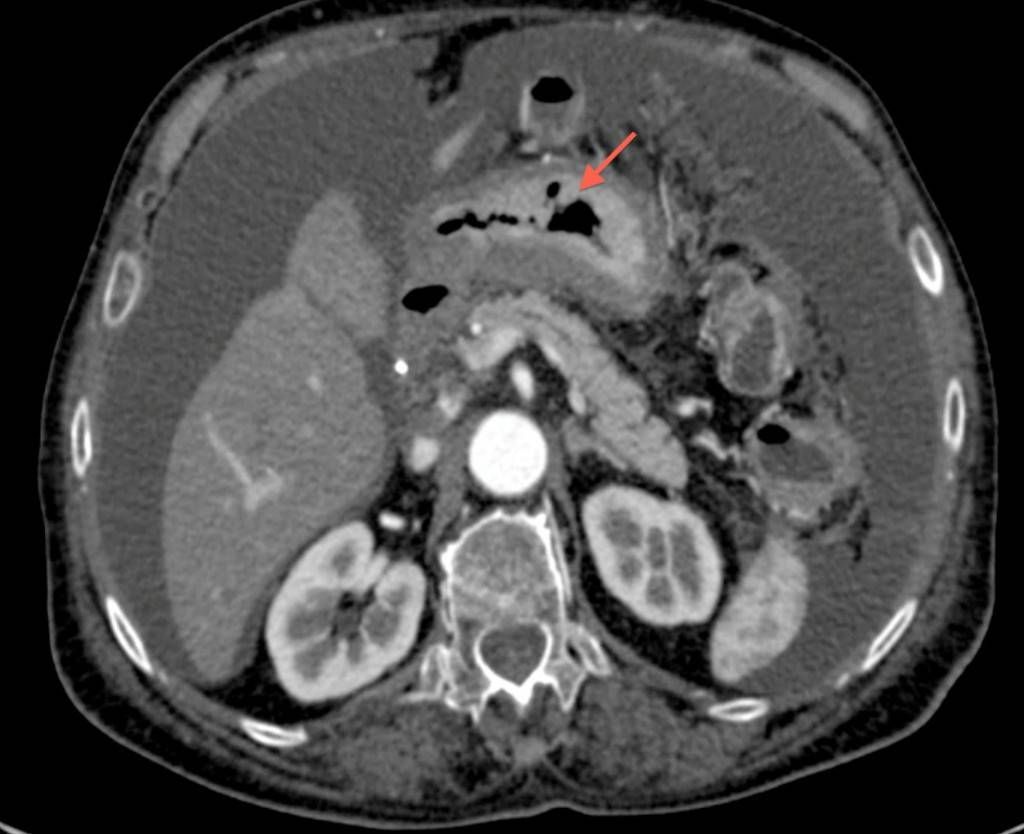

Фотографии и снимки КТ легких без контрастных веществ

Раздел: Визуальный дайджест